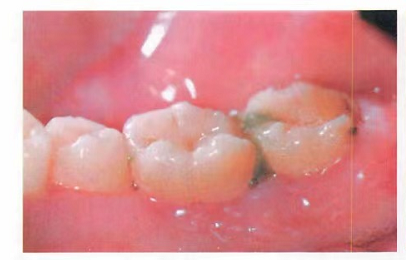

食物嵌塞

牙齦出血的炎癥和出血,牙齦呈現(xiàn)暗紅色或鮮紅色,牙齦腫脹,質(zhì)地松軟

;